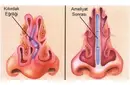

Diz Kıkırdak Belirtileri ve Tedavisi Diz kıkırdağı, diz ekleminin düzgün çalışabilmesi için kritik bir yapı oluşturur. Kıkırdak, eklem yüzeylerini kaplayarak sürtünmeyi azaltır ve hareket sırasında şok emici bir görev üstlenir. Ancak, çeşitli nedenlerden dolayı diz kıkırdağında hasar meydana gelebilir. Bu yazıda, diz kıkırdağında oluşabilecek belirtiler, bu belirtilerin nedenleri ve tedavi yöntemleri detaylı bir şekilde ele alınacaktır. Diz Kıkırdak Hasarının Belirtileri Diz kıkırdağında meydana gelen hasar, çeşitli belirtilerle kendini gösterebilir. Bu belirtiler, hasarın ciddiyetine ve nedenine bağlı olarak değişiklik gösterebilir. Yaygın belirtiler şunlardır:

Diz Kıkırdak Hasarının Tanısı Diz kıkırdak hasarının tanısı, genellikle bir ortopedi uzmanı tarafından konulur. Tanı sürecinde şu yöntemler kullanılabilir:

Diz Kıkırdak Hasarının Tedavi Yöntemleri Diz kıkırdak hasarının tedavisi, hasarın ciddiyetine ve bireyin genel sağlık durumuna bağlı olarak değişir. Tedavi yöntemleri arasında şunlar bulunmaktadır: